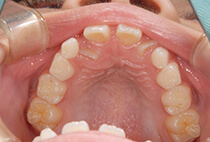

治療前

治療後

しっかり前歯を下げるために、インプラントアンカーを使用してコントロールしました。

かみ合わせが整うと咬筋の過緊張が改善。

過緊張による筋肉肥大も改善しフェイスラインもすっきりしました。